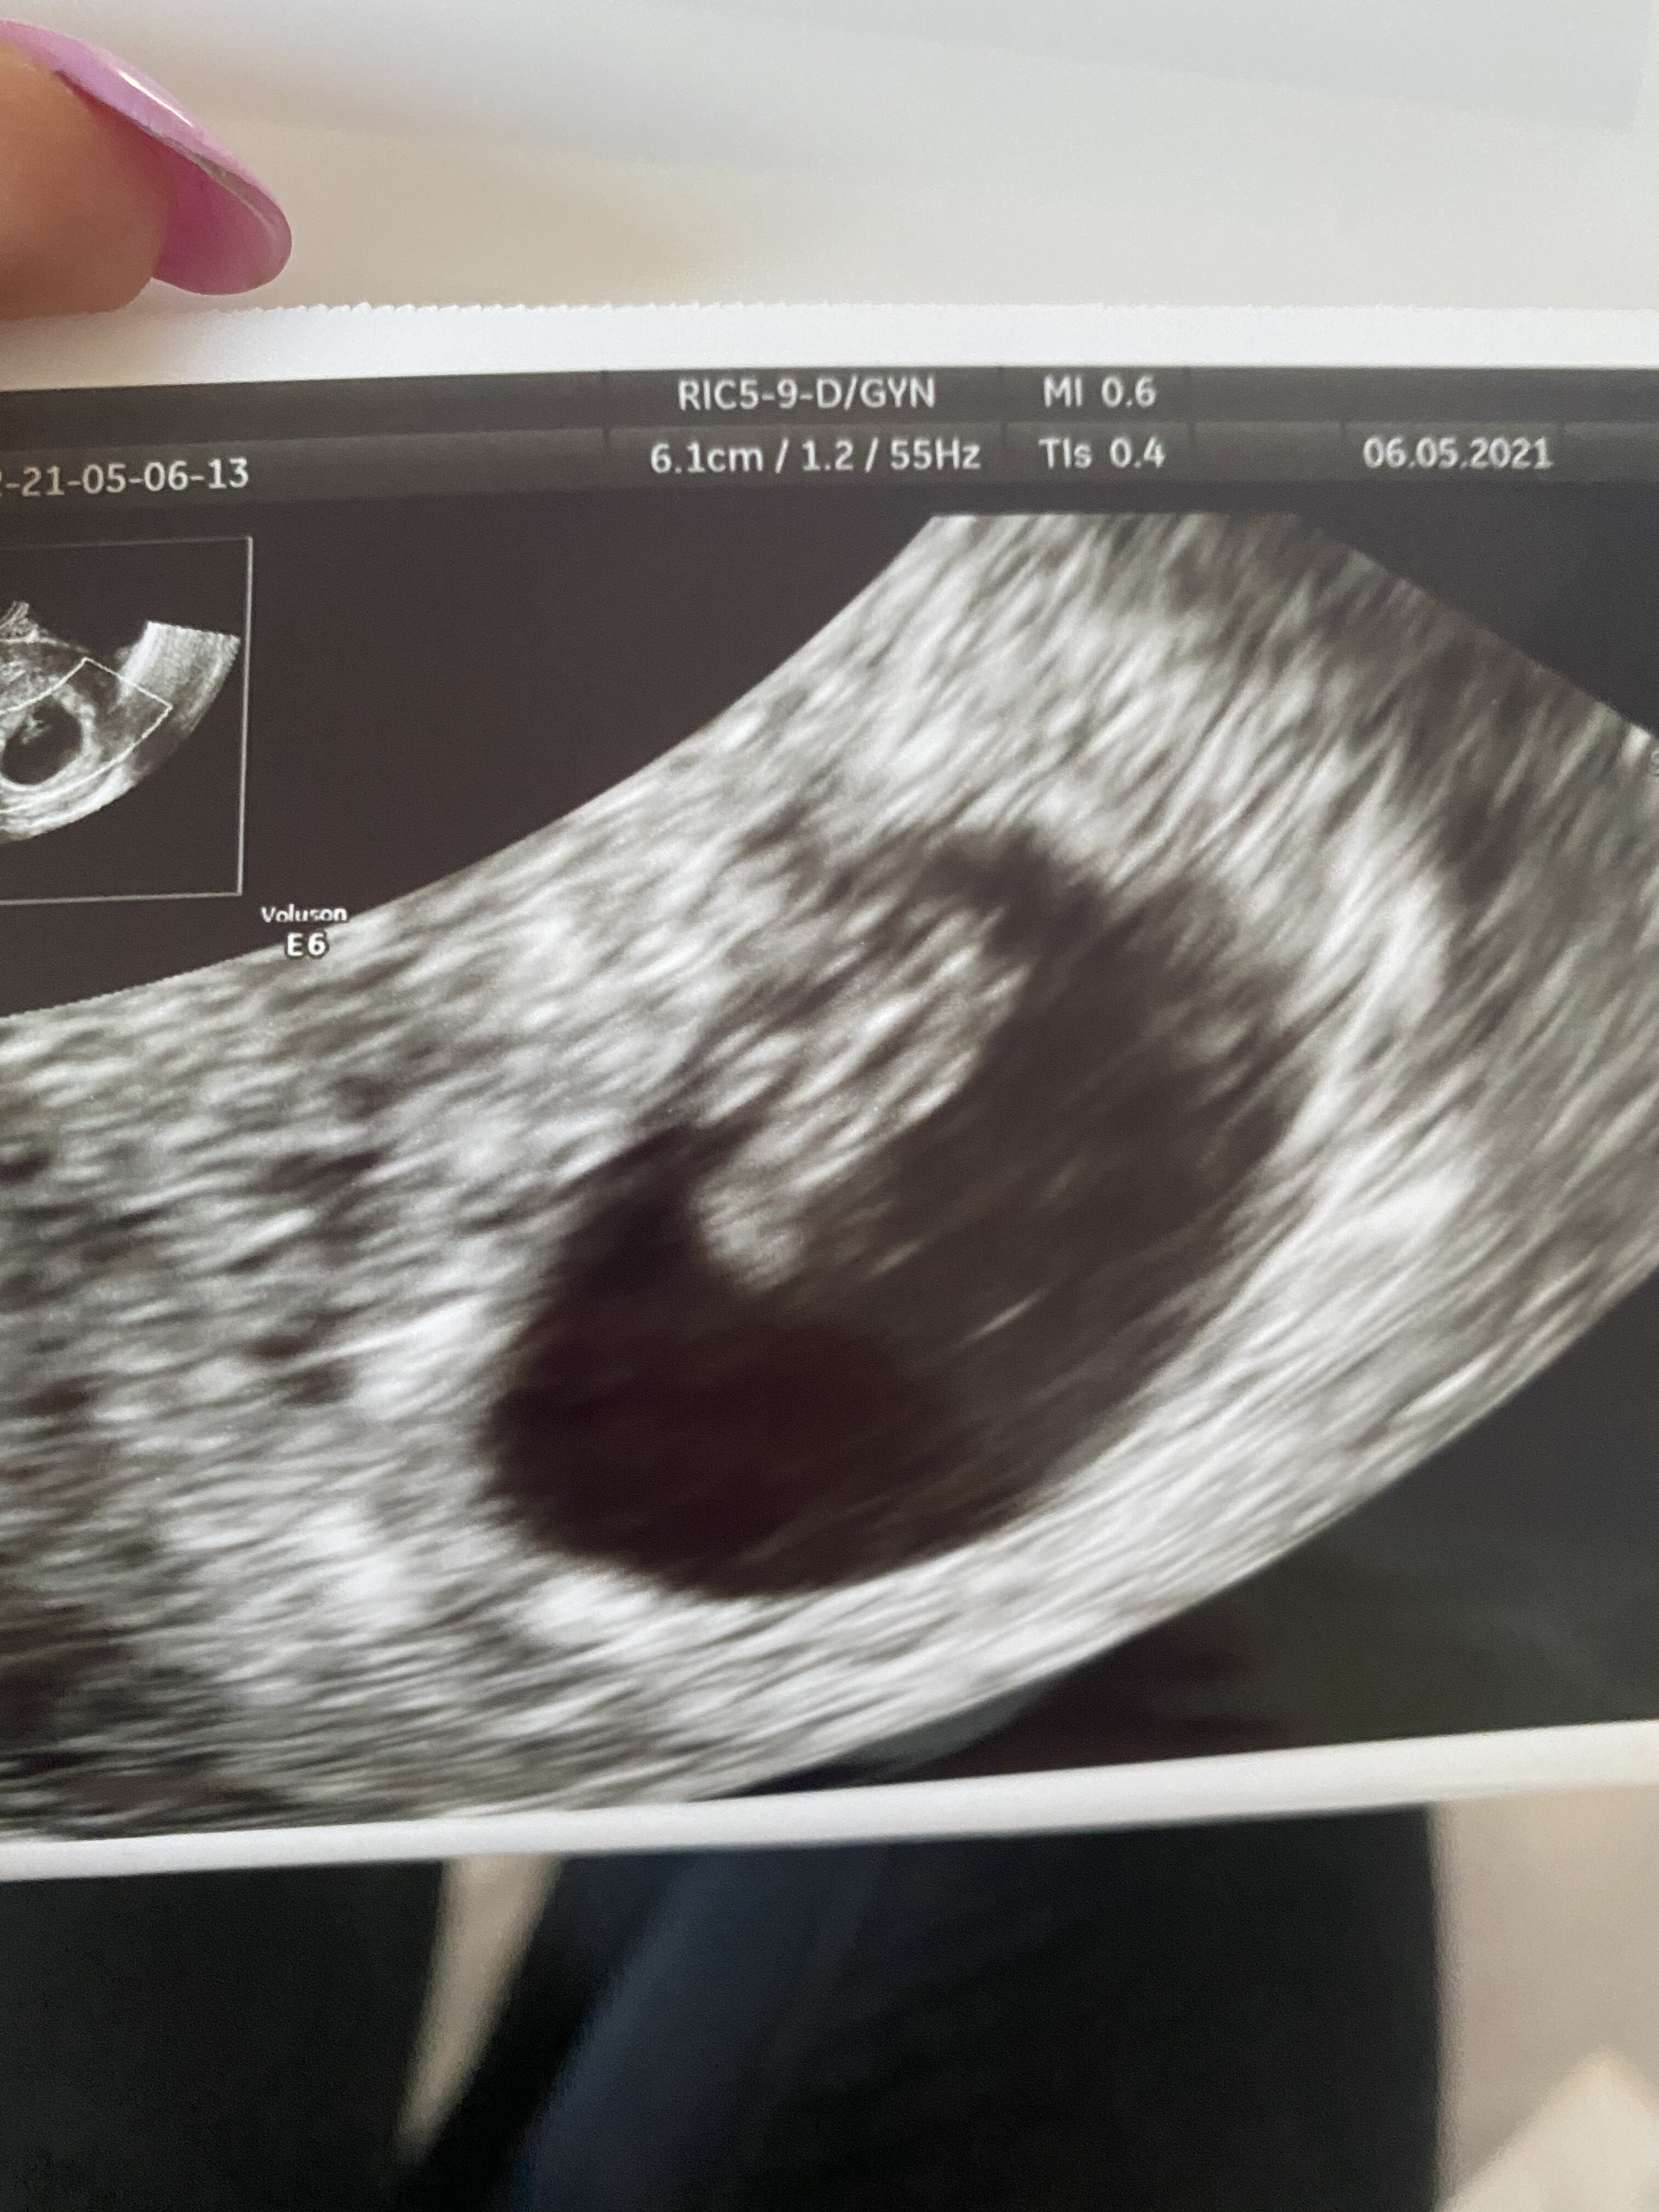

Byłam już na dwóch badaniach USG i ciąża jest w macicy, a zarodek w pęcherzyku, tyle że nadal nie słychać serduszka. Więc jeśli już, to raczej to ostatnie wchodzi w grętrochę za mało szczerze, powtórz ta betę raz jeszcze dla swojego bezpieczeństwa za dwa dni, małe przyrosty i utrzymujące się słabo rosnące beta hcg to tez może być pozamaciczna, są sytuacje, ze pęcherzyk w macicy, a zarodek gdzies indziej, rzadko bardzo się to zdarza, ale zdarza, albo beta Ci już leci w dol po prostu

Uff byłam i wszystko ok

serducho bije, z usg 7+2, mam się nie stresować, objawy mogły już mi minąć

mówi, ze wszystko już będzie dobrze bo to już duże dziecko, ma 1,14 cm